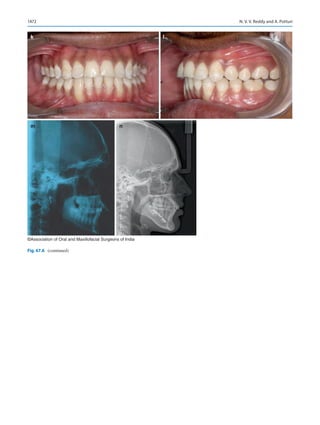

2017 Jan 16.

4.	Revised 2007 regulation of the Dental Council of India, Gazette of